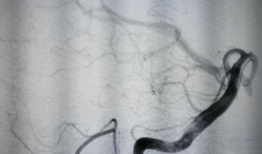

支气管镜检查,一场与呼吸的亲密对话想象你的呼吸系统就像一座神秘的迷宫,而支气管镜检查,就是一把开启这扇神秘之门的钥匙。今天,就让...